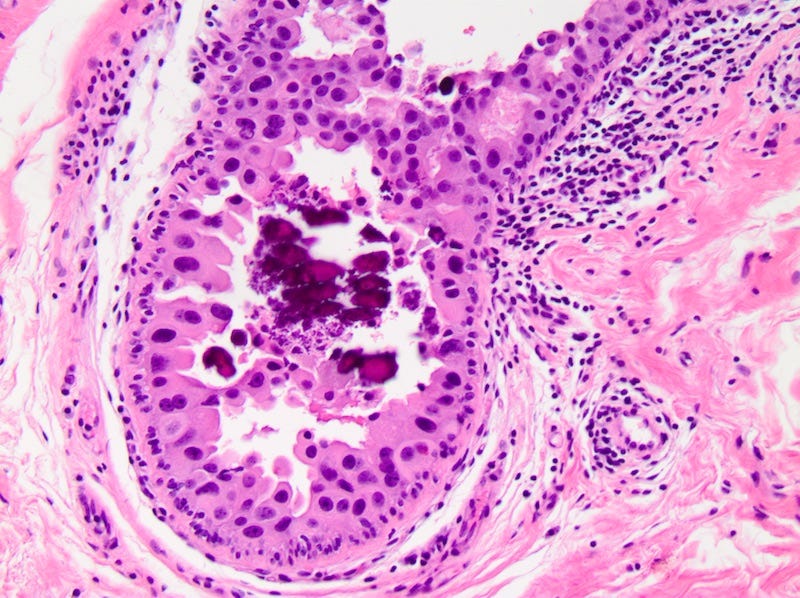

DCIS - microscopic images

Precursor of IDC - ductal carcinoma in situ (DCIS)

Ductal carcinoma in situ (DCIS) is a neoplastic proliferation of breast ductal epithelial cells within the ductal-lobular system with malignant microscopic features but without evidence of invasion through the epithelial basement membrane or myoepithelial cell layer into the surrounding stroma.

DCIS is a precursor of infiltrating duct carcinoma of no special type. It is also a precursor of tubular carcinoma, cribriform carcinoma, male invasive carcinoma and neuroendocrine carcinoma-small cell type.

DCIS includes a heterogeneous group of lesions in terms of microscopic appearance, molecular alterations, biomarker expression profile and biologic potential for progression to invasive carcinoma. It is divided into low grade (less aggressive) DCIS and high grade DCIS. Normal breast tissue appears to transform to only one of these entities through two distinct molecular pathways (i.e. high grade DCIS does not typically arise from low grade DCIS). Low grade DCIS shows frequent chromosomal losses at 16q. High grade DCIS shows frequent losses at 8p and gains at 17q and has a similar molecular profile as invasive breast cancer.

The microcalcifications that identify DCIS on mammograms are a response to cell death from either a hypoxic environment (the Warburg effect) or cell crowding due to abnormal cells growing unchecked inside the duct. When these calcifications appear on a mammogram, they often have suspicious features that require further investigation.